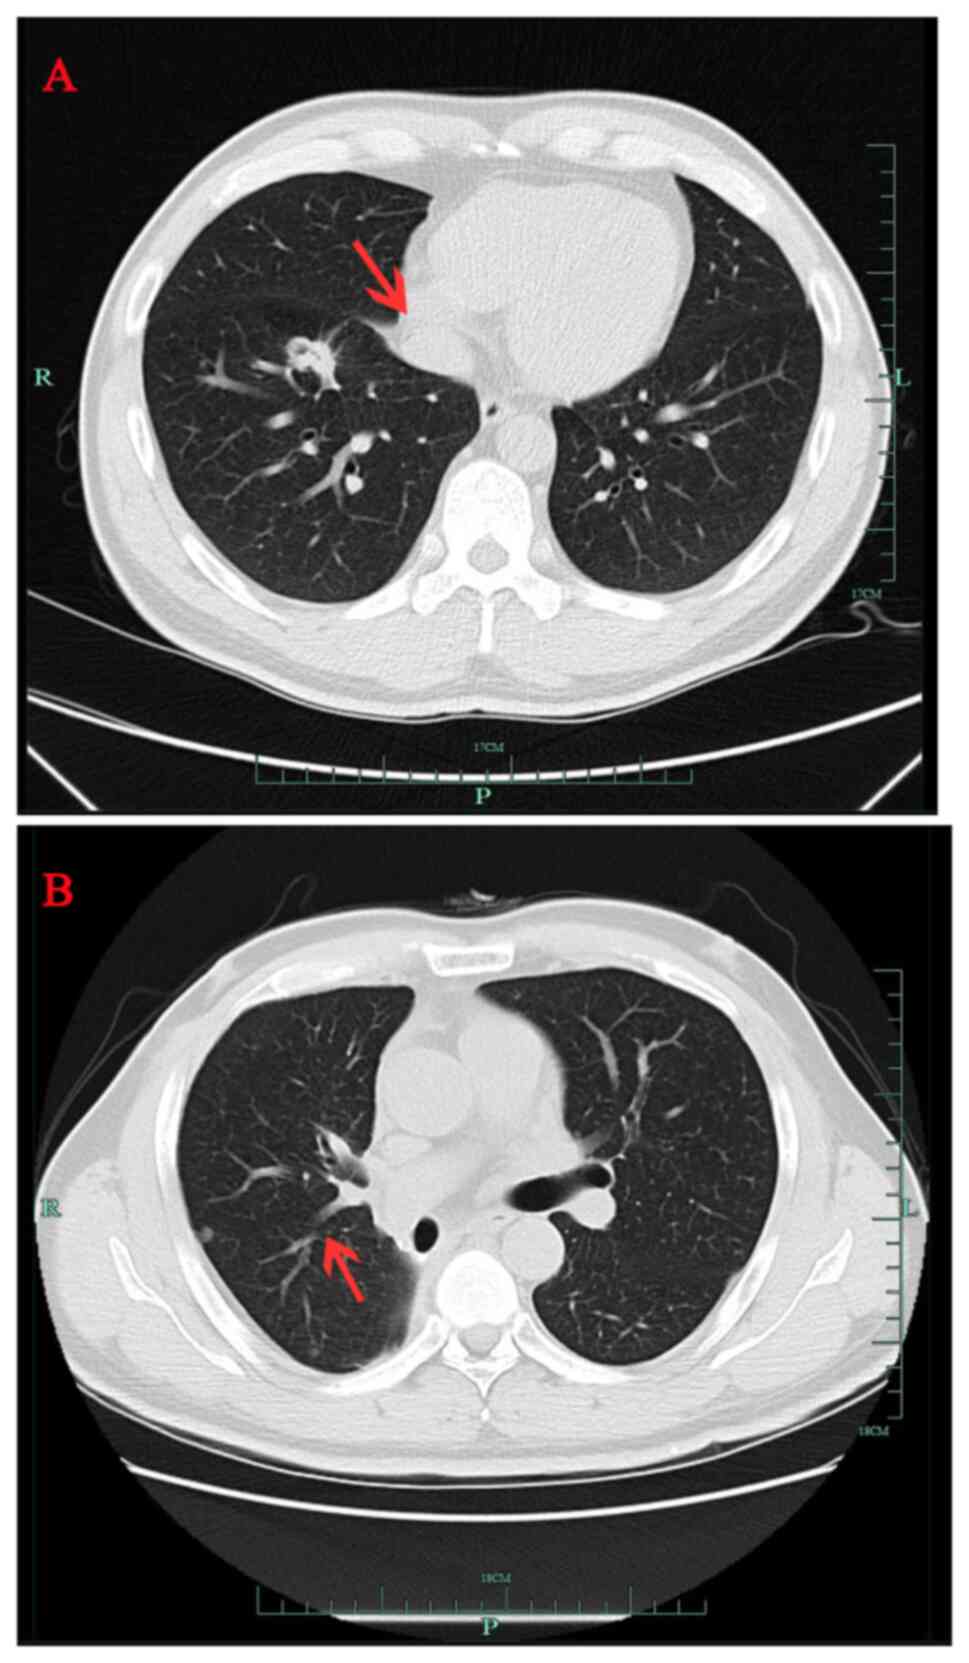

A 40-year-old male patient (healthy and non-smoker) was found to have a right lower lung space during an annual routine checkup in September 2016 (Fig. 1A) at The First Affiliated Hospital Zhejiang University School of Medicine (Hangzhou, China). The patient's father, who smoked for 40 years, had also been diagnosed with lung cancer but refused genetic testing. Radical resection of the lower right lung cancer was performed in October 2016. The pathological diagnosis was adenocarcinoma of the lower right lung (T1N2M0, stage IIIA) (38). Postoperative concurrent chemoradiotherapy included four cycles of pemetrexed + platinum, with a total radiotherapy dose of 50 Gy in 25 fractions (50 Gy/25 f). In March 2018, routine chest computed tomography (CT) scan demonstrated a new nodule near the pleura in the middle lobe of the right lung (Fig. 1B), which indicated local recurrence of adenocarcinoma. Gefitinib (250 mg, once daily) was administered orally and the nodules subsequently disappeared by July 2018, as confirmed by chest CT scan (data not shown).

Figure 1.

Serial chest CT scans of patient with non-small cell lung cancer. (A) CT scan from September 2016 showing a right lung mass (red arrow). (B) CT scan from March 2018 showing a small nodule (red arrow) near the pleura in the middle lobe of the right lung. CT, computed tomography.